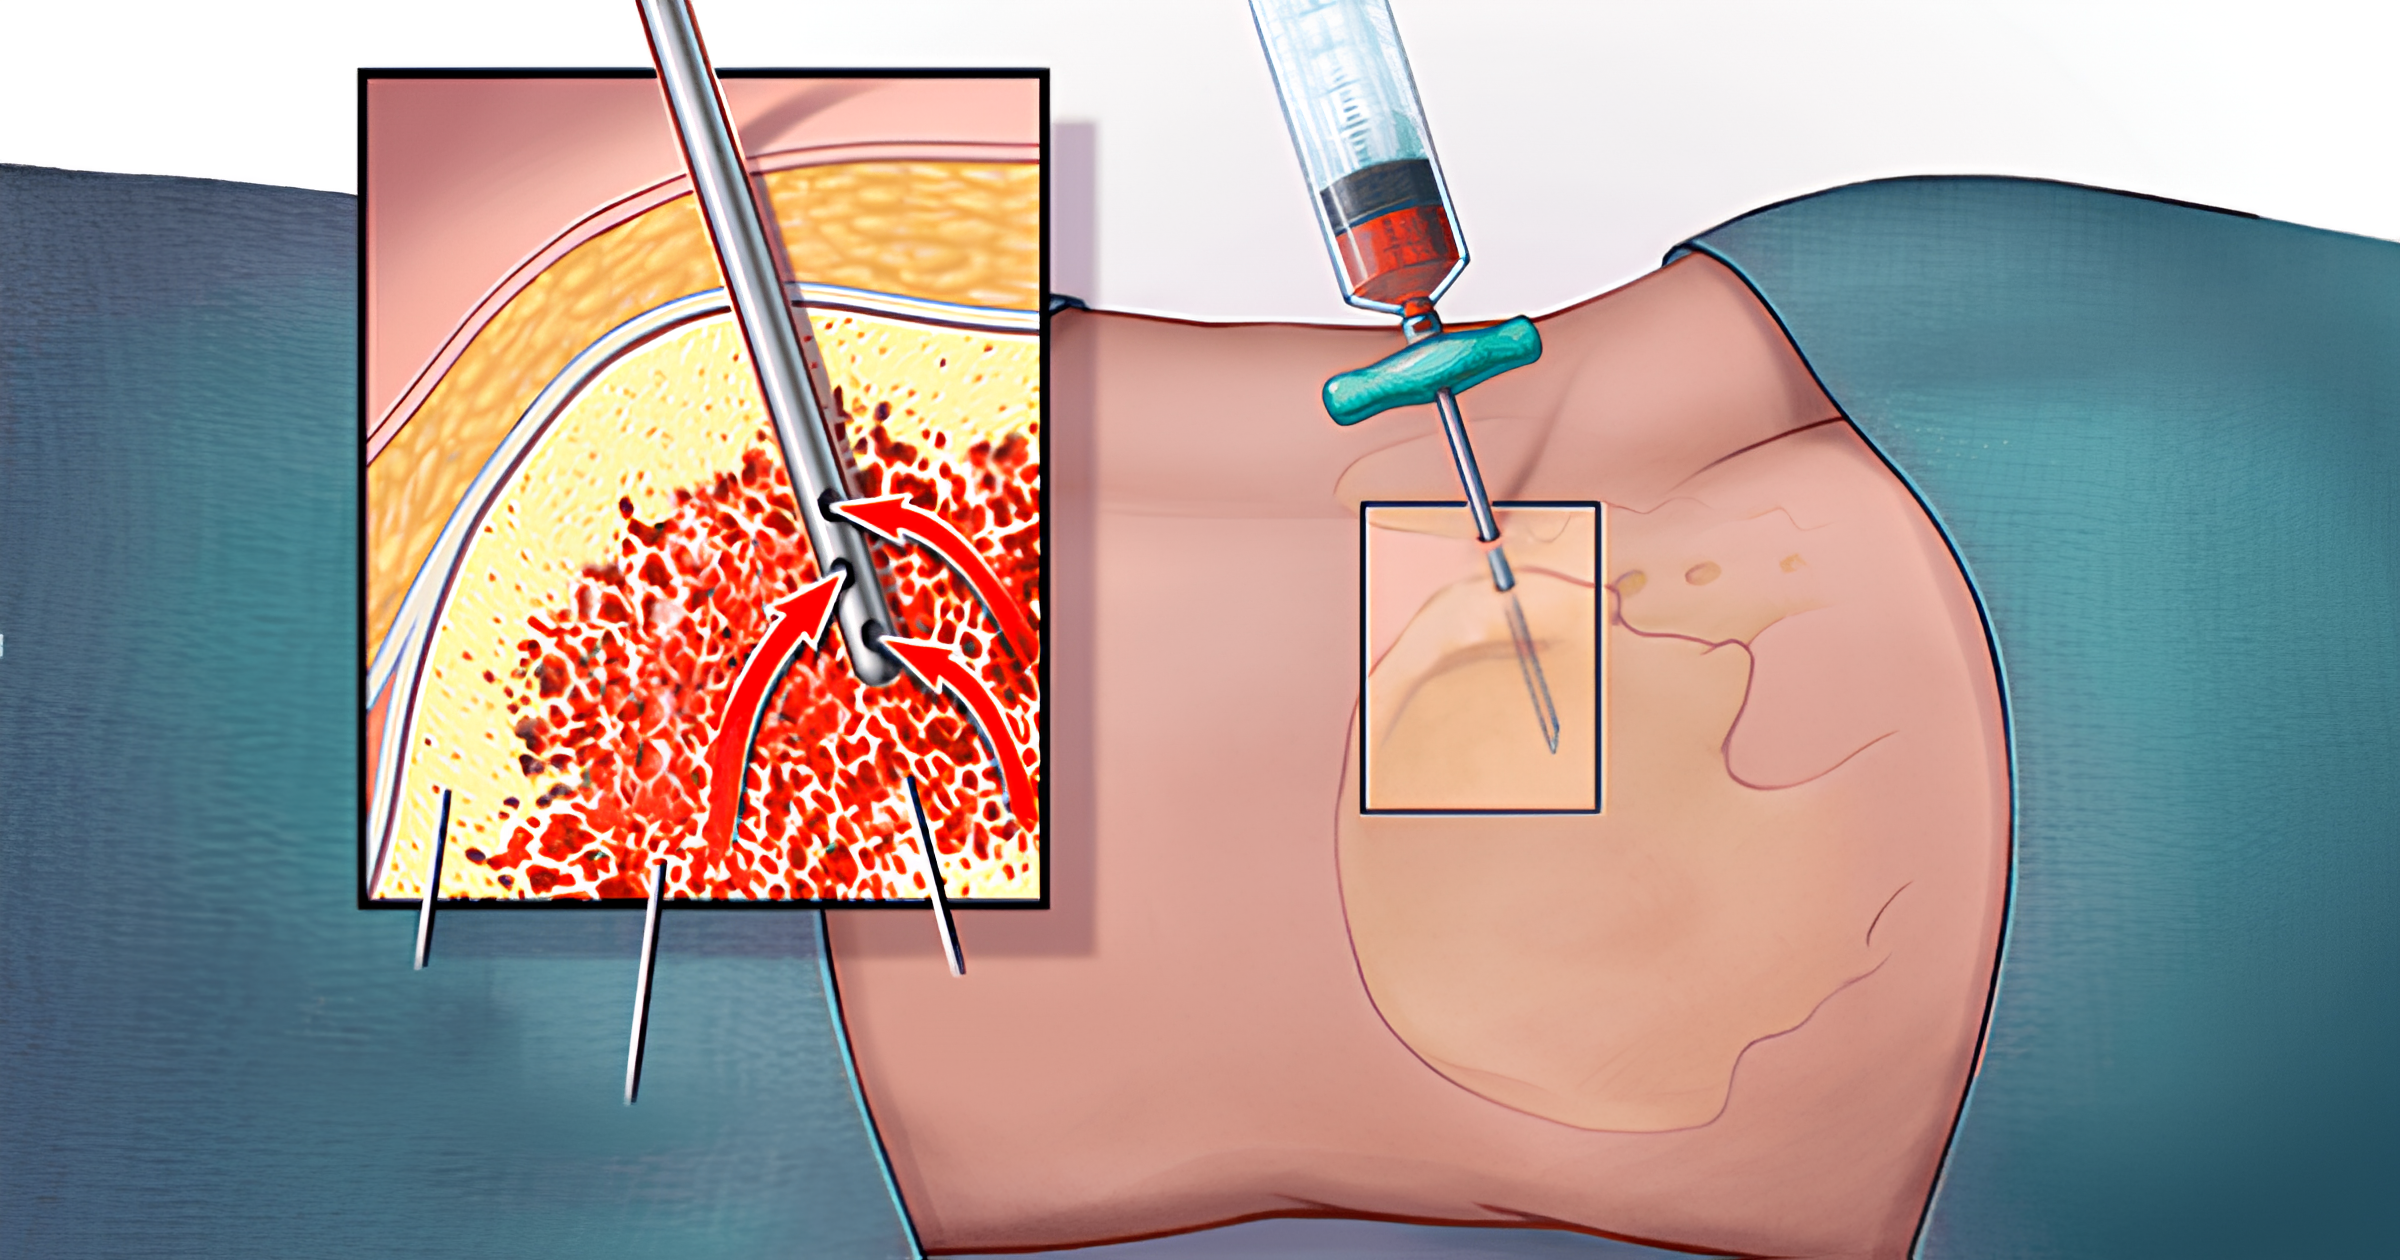

- Ghép tế bào gốc tạo máu:

- Được chỉ định cho nhóm nguy cơ trung bình hoặc cao sau khi đạt lui bệnh.

- Đây là phương pháp duy nhất có khả năng chữa khỏi lâu dài.